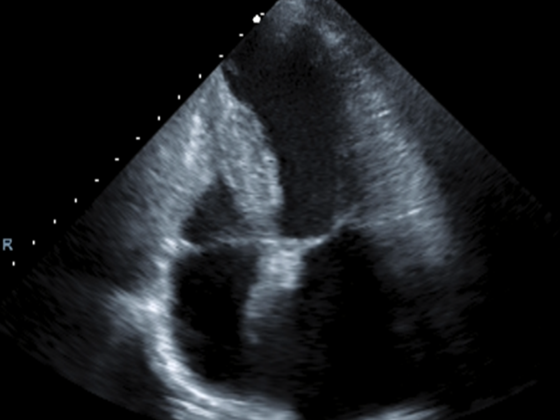

生理検査分野では、患者さんの不安をなるべく取り除くため丁寧な説明を常に心がけています。循環器に特化しており、心電図や超音波検査では多くの症例を経験し迅速な対応や知識の向上が必要と考えています。

大動脈弁(4尖弁)

心尖4腔像

検査は治療の入り口でもあり、病気の経過観察、治療効果の判定、病気の早期発見などに貢献しています。超音波検査や長時間心電図検査については予約検査と、来院された当日にも検査が受けられるように環境を整えています。来院されたその日に、検査結果を報告しより迅速に治療に繋げられるに努めています。